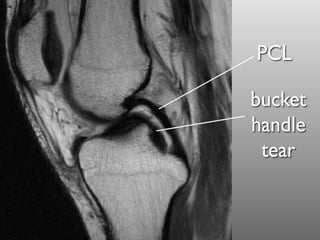

Classification

• Descriptive classification

– location

• red zone (outer third, vascularized)

• red-white zone (middle third)

• white zone (inner third, avascular)

– size

– pattern

1. vertical/longitudinal

2. bucket handle

3. oblique/flap/parrot beak

4. radial

5. horizontal

6. complex

Classification • Descriptiveclassification – location • red zone (outer third, vascularized) • red-white zone (middle third) • white zone (inner third, avascular) – size – pattern 1. vertical/longitudinal 2. bucket handle 3. oblique/flap/parrot beak 4. radial 5. horizontal 6. complex

• #21 pattern Vertical or longitudinal is more common, especially with ACL tears repair when peripheral bucket handle vertical tear which may displace into the notch. oblique/flap/parrot beak may cause mechanical locking symptoms. radial horizontal more common in older population may be associated with meniscal cysts

• #27 The double PCL sign appears on sagittal MRI images of the knee when there is a bucket-handle tear of the meniscus